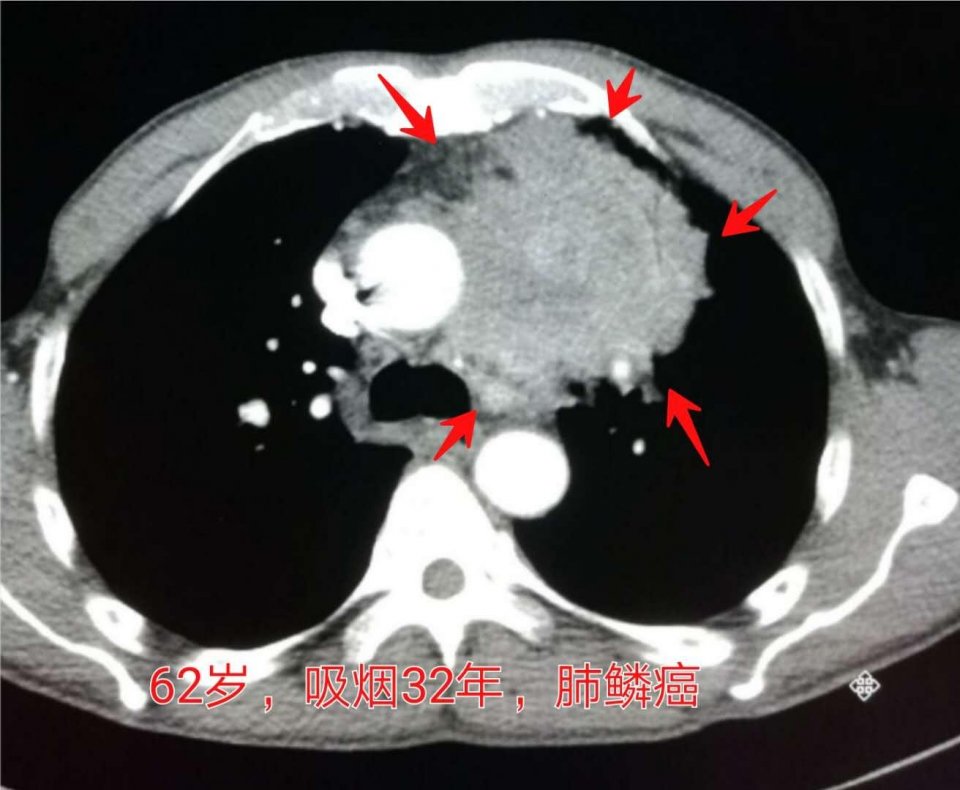

2.男性病人,62岁,吸烟32年,咳嗽、胸痛一个多月:

这位老爷子是一年前查出晚期肺鳞癌,今年来复查,病灶又增大了很多,很难熬到年末了。